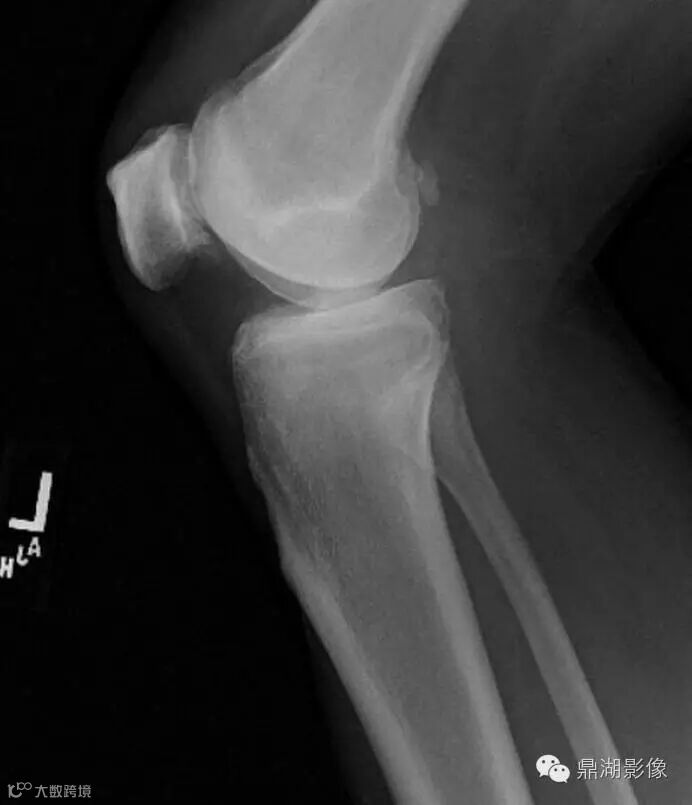

2.1 What is the most accurate explanation for the difference between the current lateral knee radiograph (Figure 1) and lateral radiograph (Figure 2) obtained 2 years earlier?

C. A calcified body within the inferior recess of a dissecting Baker cyst

Yes, the answer is C

C. The calcified body has migrated distally from its original position posterior to the femoral condyles.

Lateral view of the left knee demonstrates joint-space narrowing (yellow arrow) and chondrocalcinosis (blue arrow). There is a calcified body (white arrow) within the inferior recess of a dissecting Baker cyst.

Lateral view of the left knee from two years prior shows the body positioned posterior to the femoral condyles (white arrow).